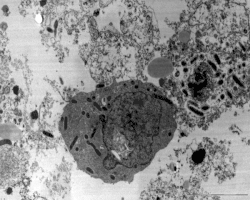

Rickettsiose ou riquetsiose refere-se a qualquer doença infecciosa causada por bactérias gram-negativas da família Rickettsiaceae e que são transmitidas por carrapatos, ácaros ou piolhos.[1]

No Brasil, a febre maculosa brasileira (FMB) é a riquetsiose mais problemática. Causada pelo Rickettsia rickettsii, um parasita intracelular obrigatório, preferencialmente de células do endotélio e transmitido pelo carrapato Amblyomma cajennense.[1] Surtos em ambientes rurais ou de mata nativa onde os carrapatos e piolhos vetores vivem ocorrem de vez em quando na América Latina e África.